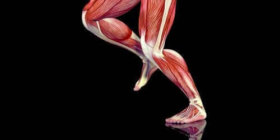

오늘은 연조직 손상을 치료하는 방법을 알아보자. 힘줄, 인대 및 근육 등 연조직 손상은 근골격계의 부드러운 부분에서 발생한다. 근육은 탄력성으로 인해 단축, 수축 및 신축이 가능한 섬유 집합으로 이루어져 있다. 반면 힘줄은 근육과 뼈를 연결하는 근육의 일부이다. 힘줄은 뼈로 에너지를 전달하여…